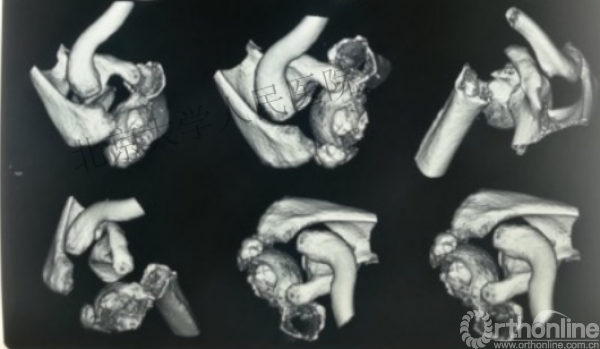

内侧皮质粉碎,低位外科颈骨折,肱骨头-干角维持困难。

术后复位丢失,肱骨头内翻畸形。

能否该偏心固定(钢板)为髓内固定,增加力臂?

此时对比髓内钉是不是有很大优势?